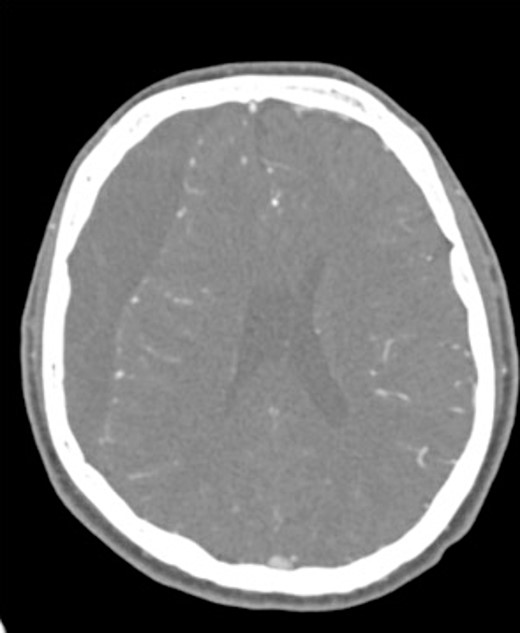

A 60-year-old male with cSDH presented to a Level I trauma center with lethargy, headaches, and left-sided hemiparesis. CT demonstrated thickened membranes and midline shift (Fig. 1).